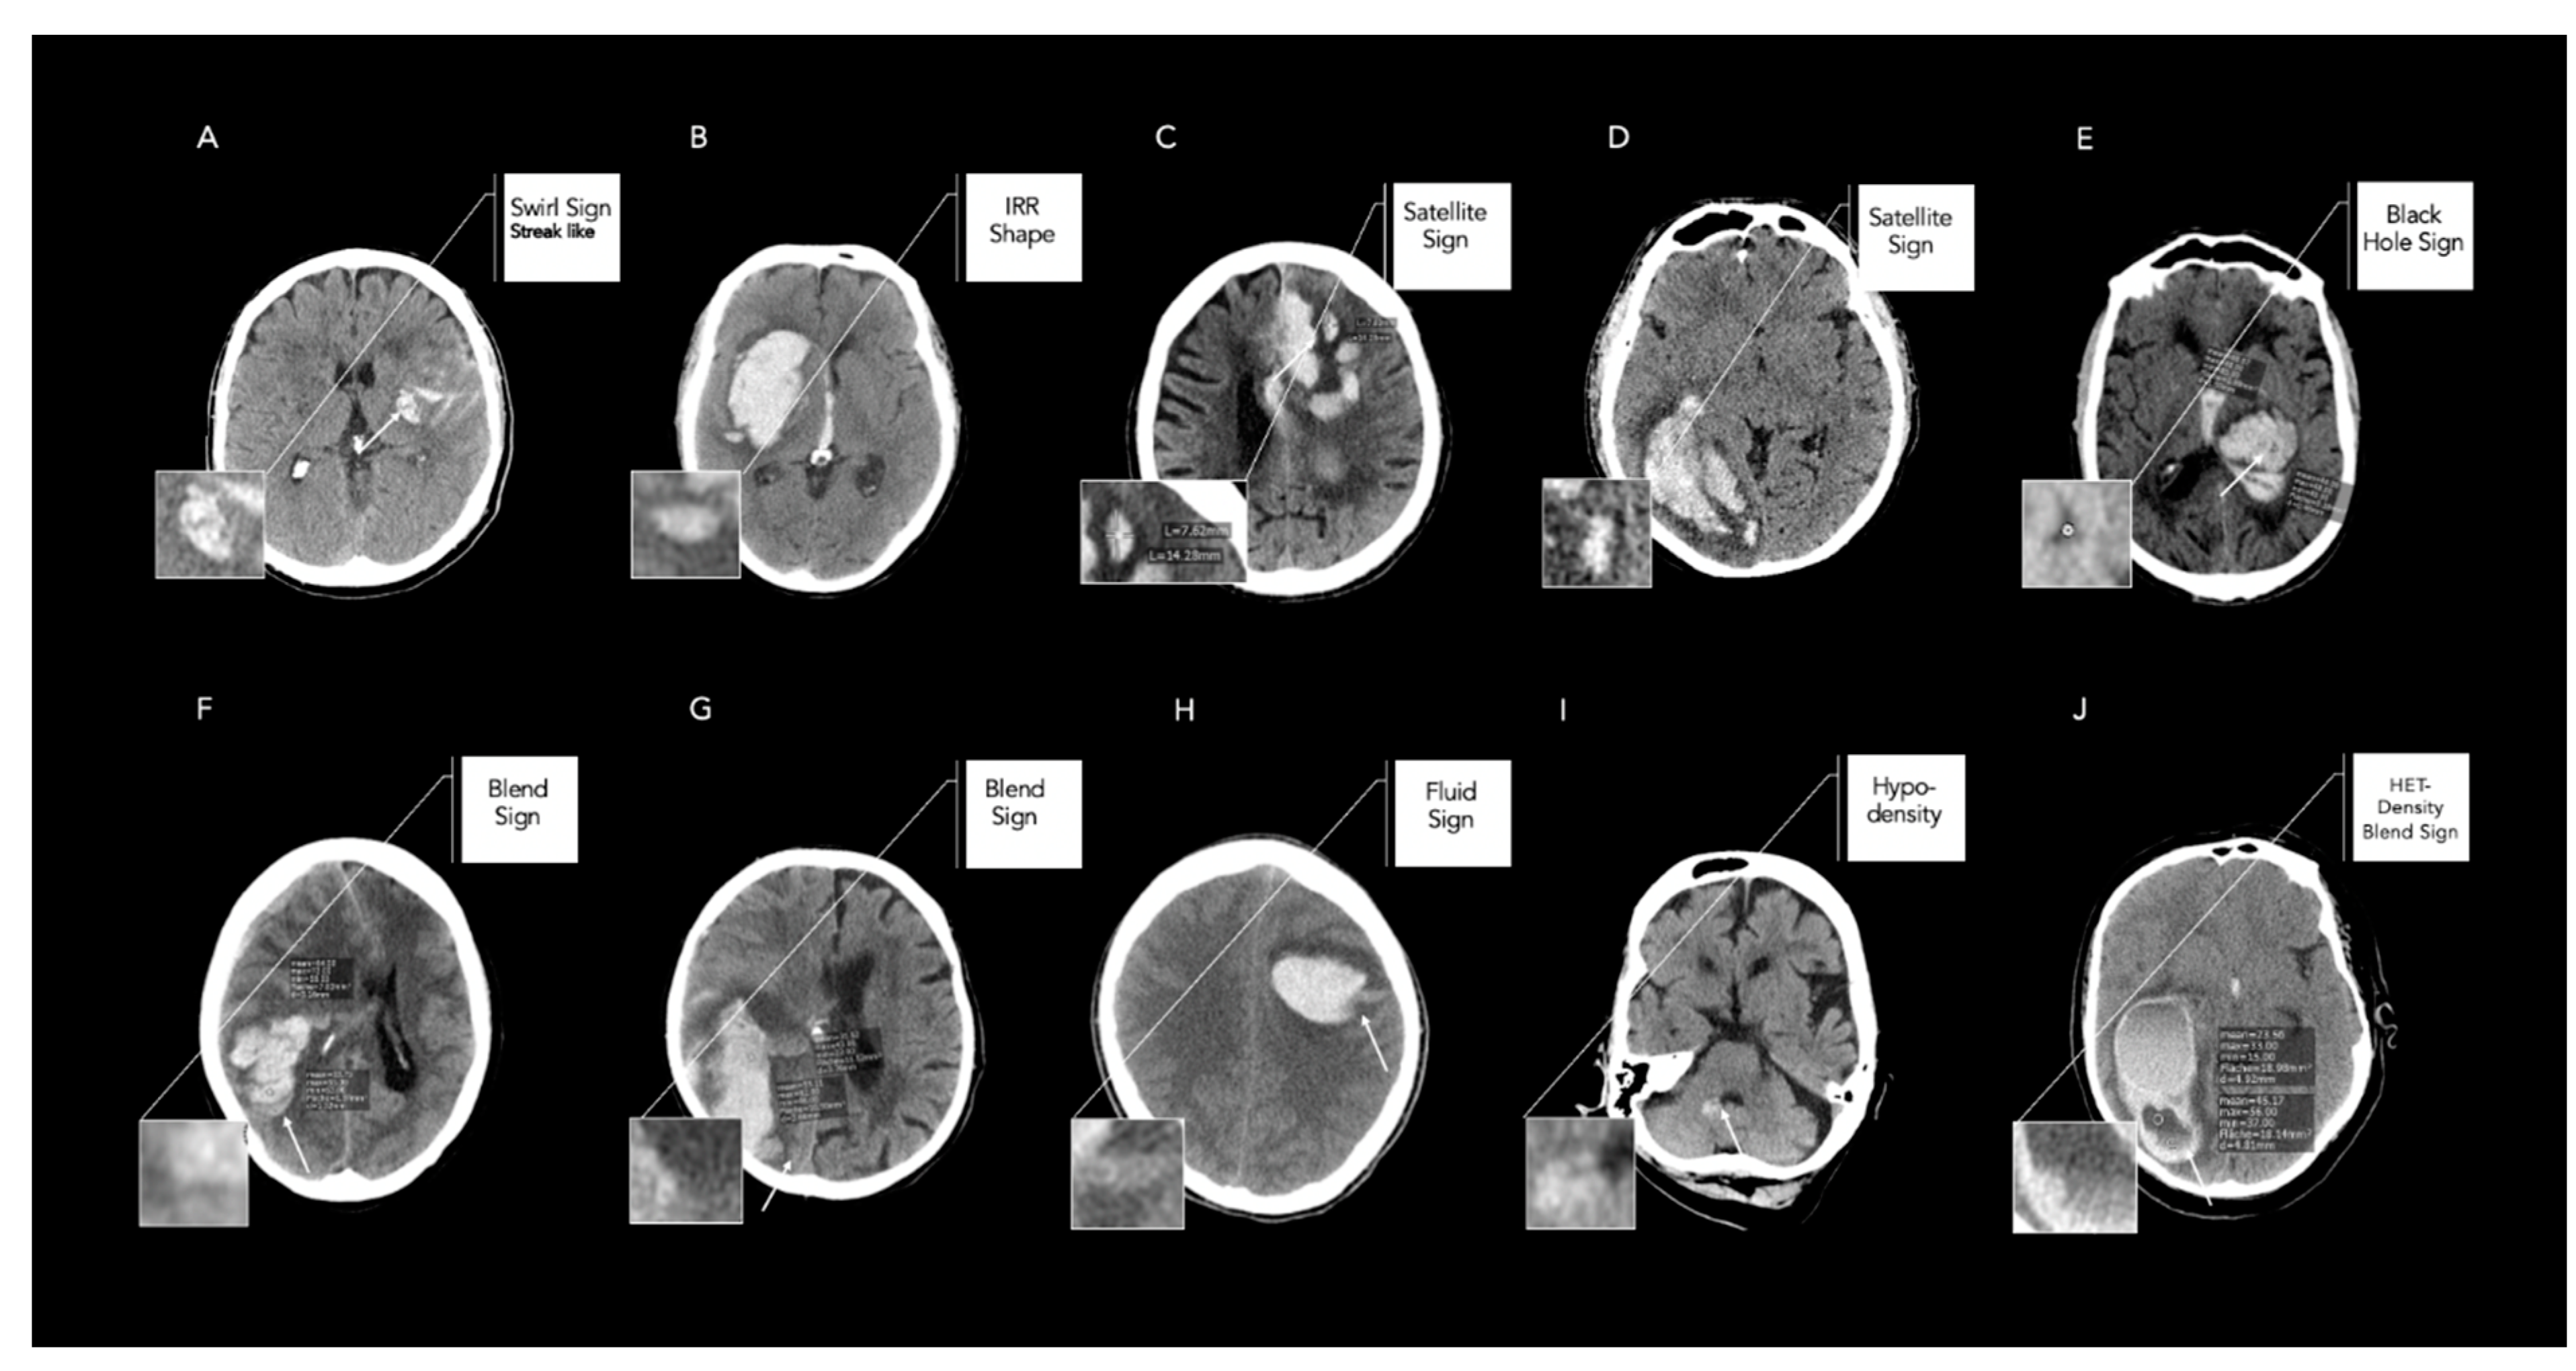

1. Introduction

2.2. Image Analysis